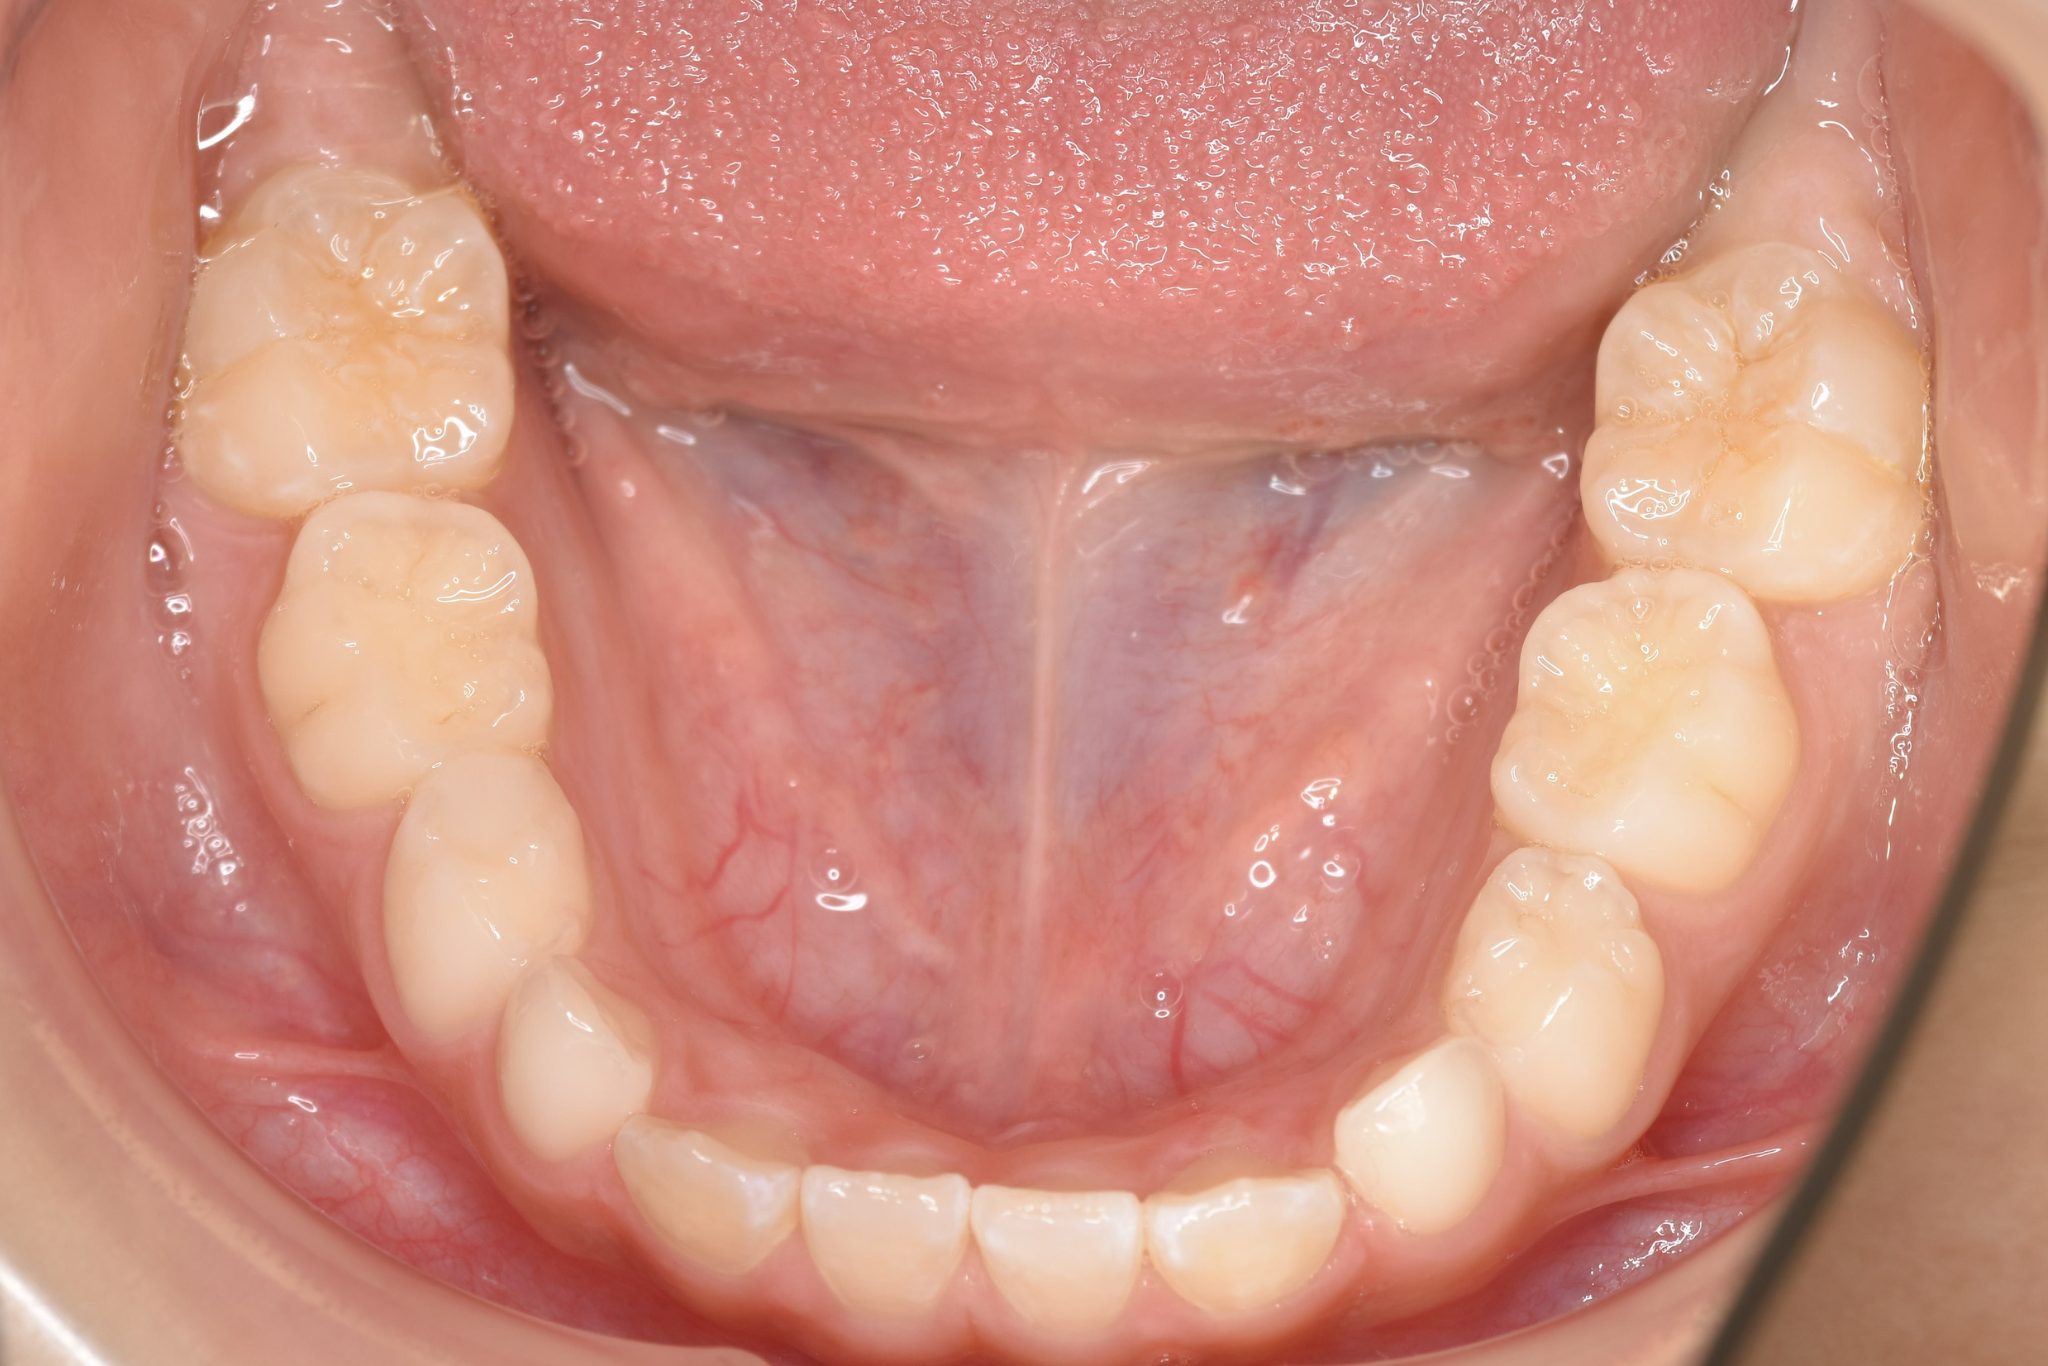

ビフォー

子どもの矯正治療|症例_858